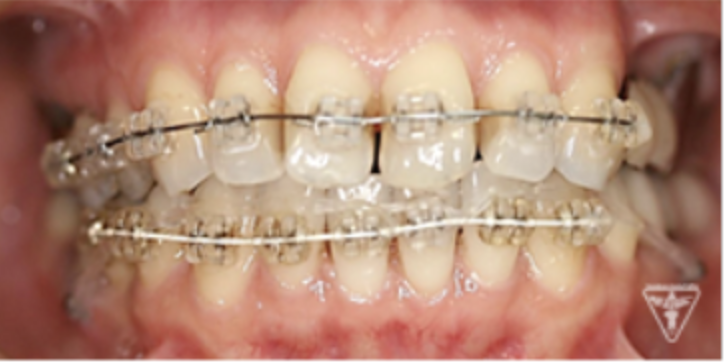

矯正治療

矯正治療による歯軸、叢生改善